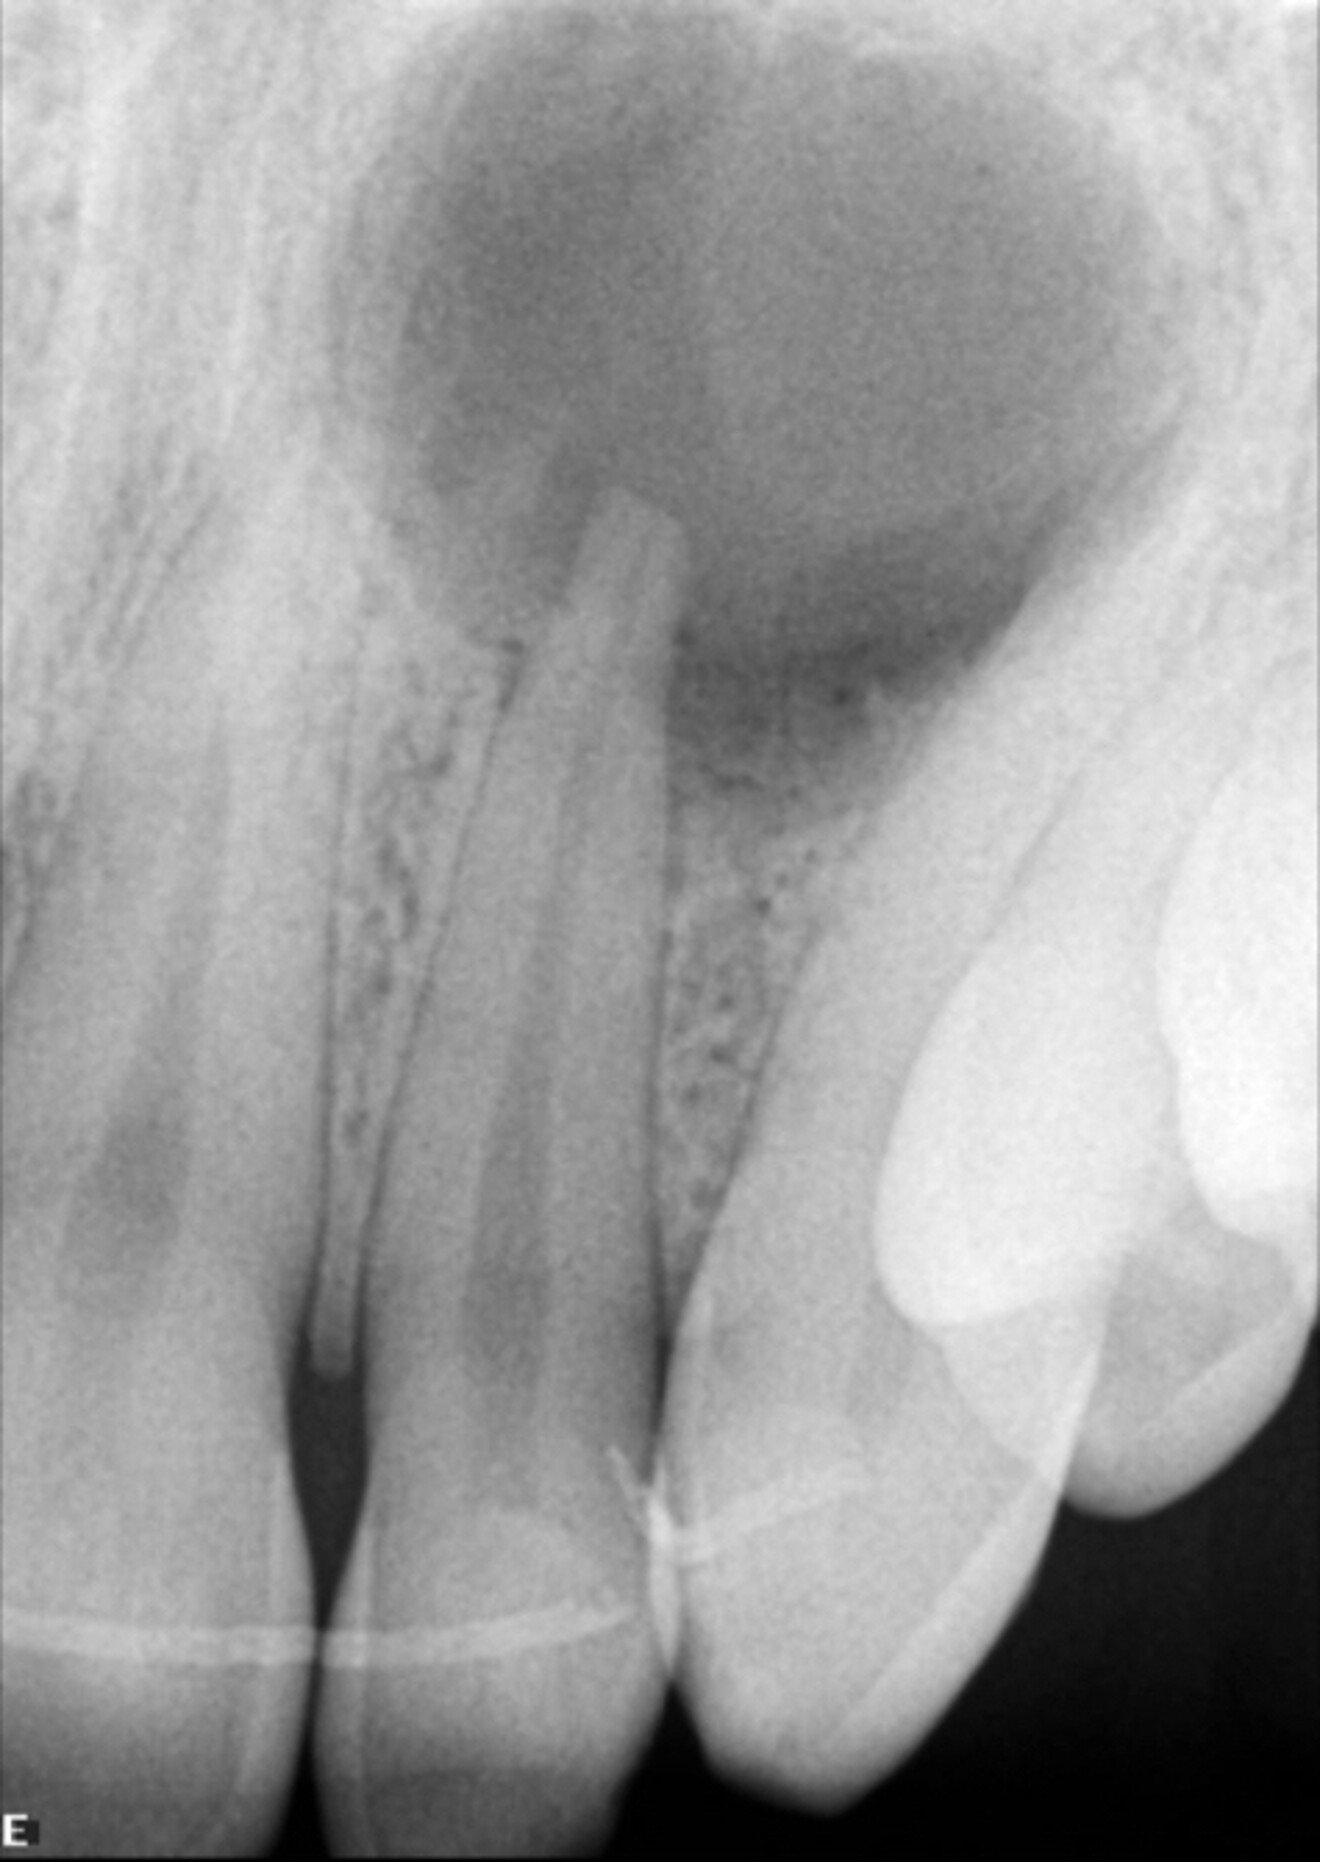

The patient presented for assessment of a fistula in the anterior maxilla on a radiograph, appearing as a large lesion above the lateral incisor (Fig. 1). The patient recalled having been hit by a ball a long time before. A CBCT scan was taken, and it showed a large cystic lesion destroying a large portion of the anterior maxilla. Owing to the edge-enhancing capability of the DTX software provided by artificial intelligence, we can enhance the quality of the image. Since the CBCT scan was taken in a different centre, we imported the DICOM file into the DTX software. The image clearly showed the nerve entering the central incisor and a thin layer of bone covering the apex, and the nerve and periodontal ligament in this area were intact (Fig. 2).

At the two-year follow-up appointment, the radiograph showed healing, but there appeared to be a superimposed image at the apex (Fig. 5). A high-definition CBCT scan taken with the DEXIS OP 3D showed that this was not a lesion but fibrous tissue consistent with physiological healing from the palatal area where the cortical plate had been largely damaged (Fig. 6). Since this was not pathological but a normal reparative process, there was no need to interfere.

Fig. 5a: Initial radiograph.

Fig. 5b: Radiograph at six months.

Fig. 5c: Radiograph at two years, showing an area of less bone condensation at the root.